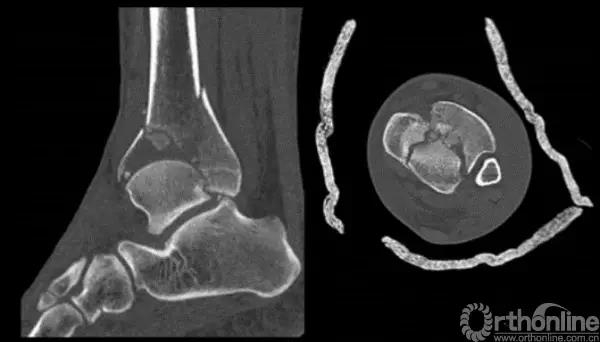

Pilon骨折手术入路选择原则一般取决于最适合进行关节面复位的入路。cole在2013年jot发表的文章描述了pilon骨折的骨折线图根据多例病例汇总到一起,颜色越深则越骨折线经过的可能性越大。

他将pilon骨折大致的骨块进行了分类,分别为后、前内、前外三个骨折块。Pilon骨折的入路一共有5个,前内、前正中、前外、后内、后外。

针对该类骨折一般采取小块靠大块的原则,充分显露之后,先从后面开始,逐步把小块往大块上复位,逐渐复位到最前面。

2.中心粉碎骨折

对于中心粉碎骨折需要充分牵引、撑开,将关节面的骨折块先找到摆放在合适的位置,用克氏针将关节面的骨块应用排筏技术先固定好,从下方观察关节面的复位情况,并且确认骨块不会向上推起,适当植骨,然后将骨块前后和左右进行压实后进行固定。